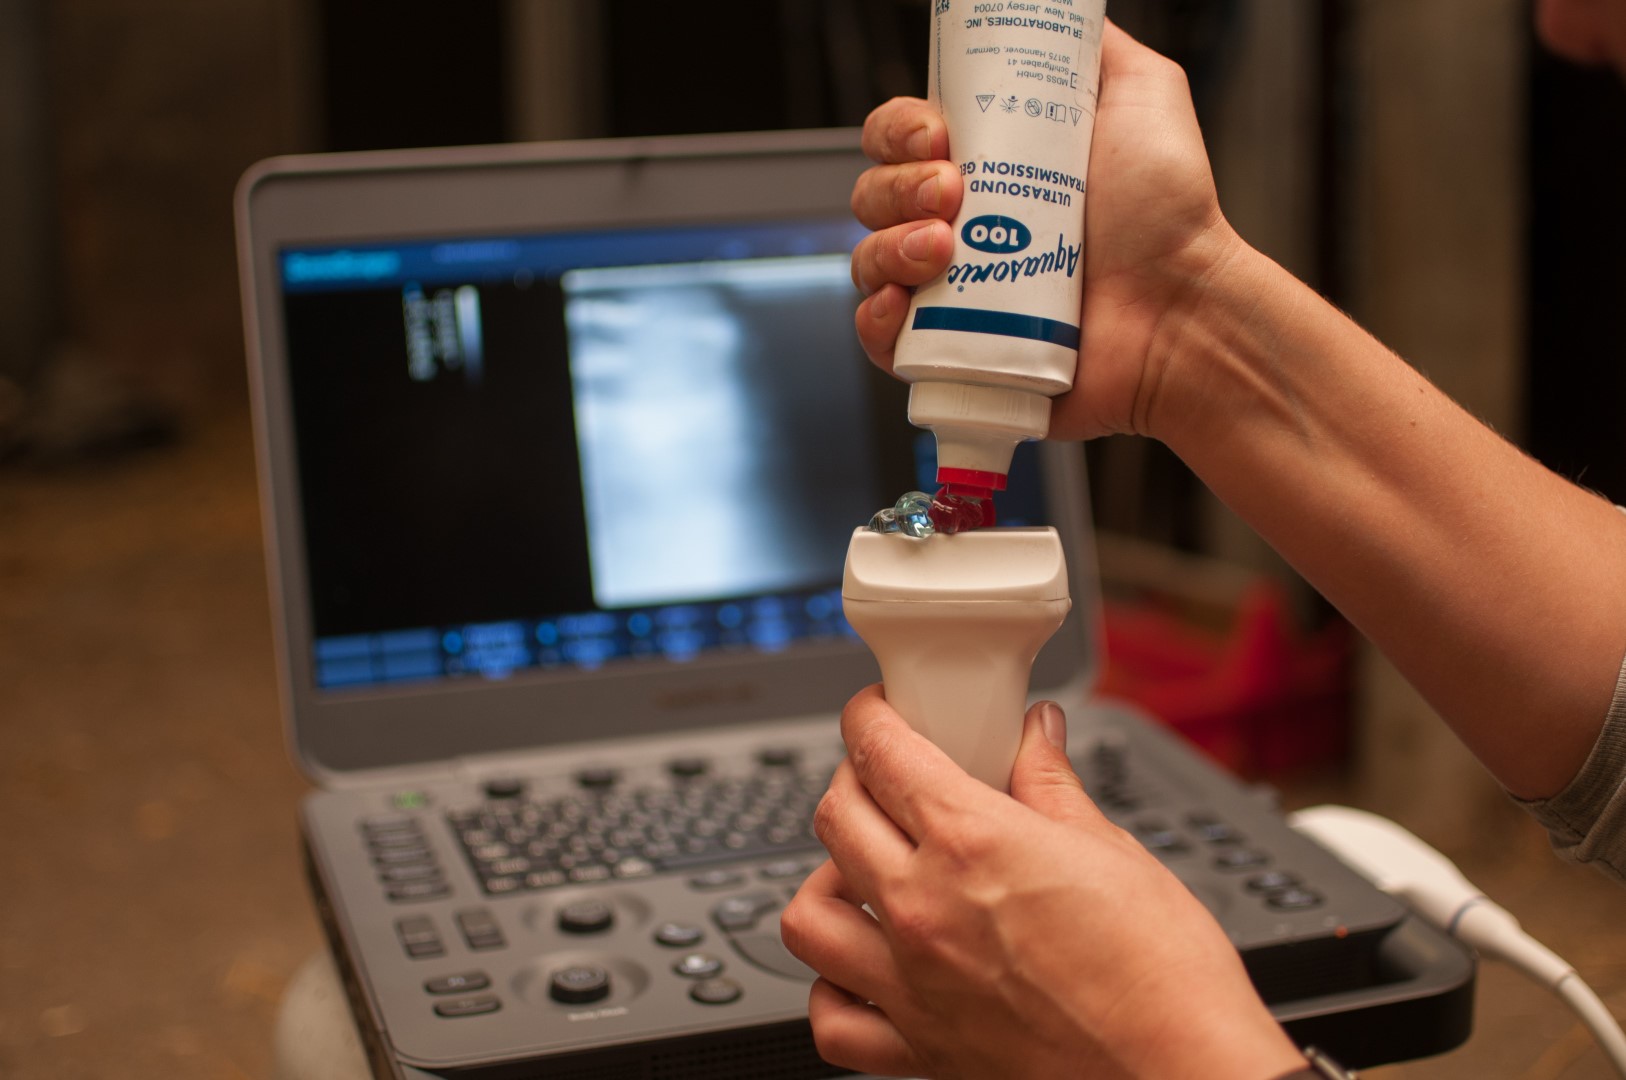

Problemen van het bewegingsstelsel uiten zich meestal door manken. Een correct mankheidsonderzoek bestaat uit een grondig klinisch onderzoek met inspectie, palpatie en een bewegingsonderzoek, al dan niet aangevuld met diagnostische lokale verdovingen. Om een adequate behandeling en een volledige diagnose te stellen, wordt er vaak gebruik gemaakt van gepaste beeldvormingstechnieken (radiografie en echografie). Aan de hand hiervan wordt er een behandelingsschema opgesteld, gevolgd door aangepast trainingsschema om uw paard zo snel mogelijk op het juiste pad te helpen.